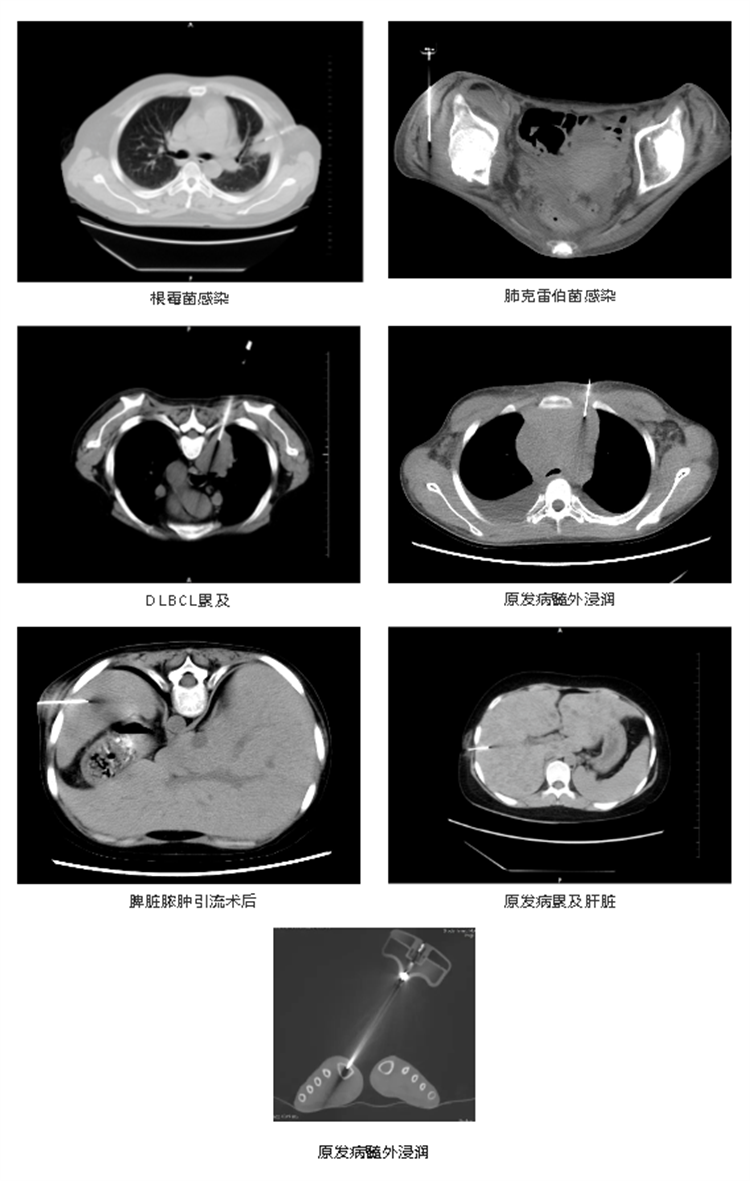

實際病例展示

657812bb507a7.png

657812c4e76c1.jpg

此項技術(shù)傷口創(chuàng)面小,對患者來說,經(jīng)濟(jì)適用,也可以為臨床治療和預(yù)后判斷提供更多的病理學(xué)信息和依據(jù)。